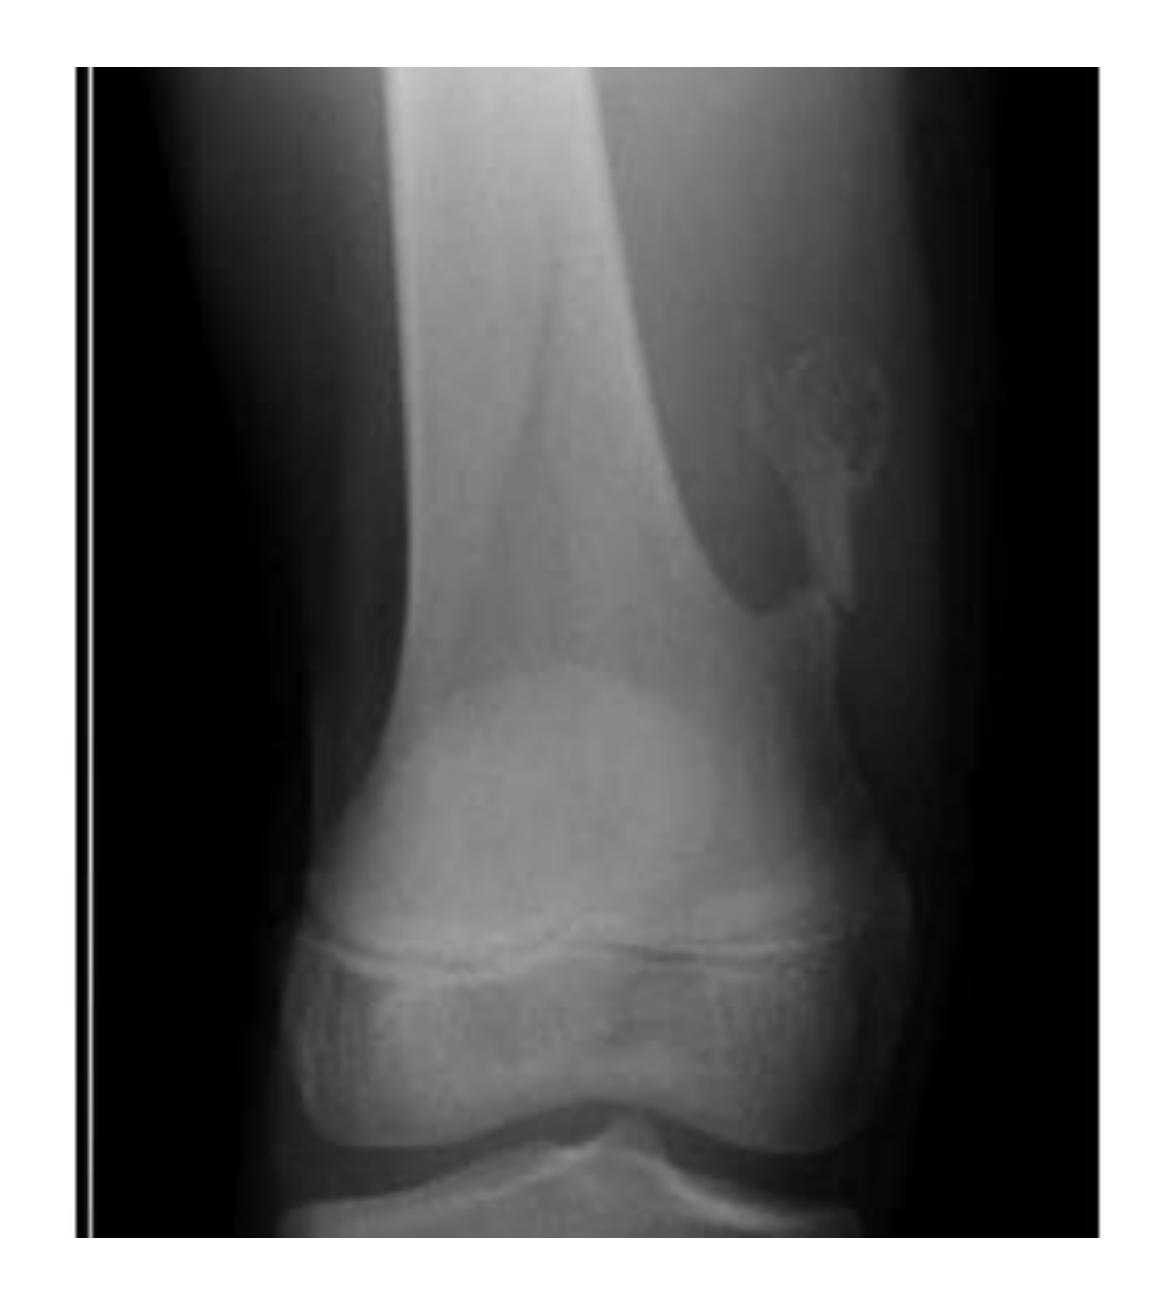

What anatomical structure is indicated by the blue arrow in a patient with chronic osteomyelitis?

- a. Involucrum

16- The blue arrow show?

A. Involucrum